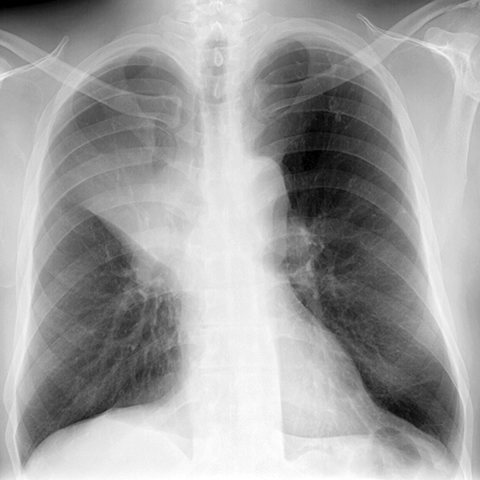

RUL Atelectasis, Consolidation and Cancer [1 of 3]